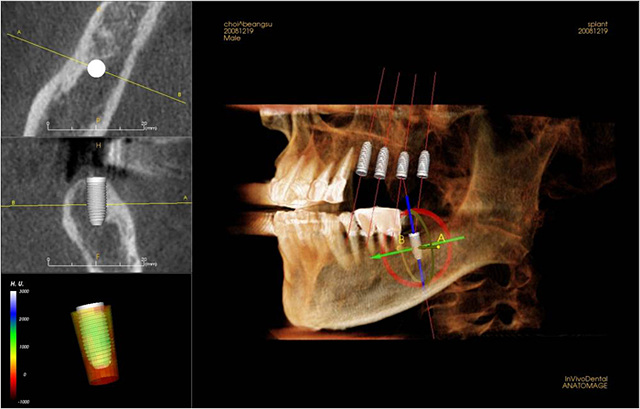

실제로 에스플란트에 내원하셨던 50대 남성 환자분의 사례를 토대로 더 자세한 설명을 드리겠습니다. 이 환자분께서는 사업상 워낙 바빠서 한참 동안 치료를 미루고 있었습니다. 증상으로는 잇몸에서 피가 나고 치아가 흔들리고 찬물을 마시면 여러 개의 치아가 시리다고 하였습니다. 먼저 3차원 CT 촬영을 하고 판독해 본 결과 구강 전반에 걸쳐 만성 치주염이 확인되었고 3개의 치아에서 치수를 침범하는 심한 충치가 발견되었습니다.

이렇게 빠르고 정확한 치료가 가능한 이유 첫 번째, 디지털 장비의 정확한 분석입니다. 정확한 진단과 분석은 치료의 기본이죠. 3D 디지털 CT와 3D 보철 스캐너를 통해 정확한 진단과 계획이 가능하여 즉시 기능이 가능한 임플란트 치료 준비와 당일 임플란트 치료가 가능한 것입니다.

마지막으로 철저한 계획과 가이드 제작입니다. 환자분의 이해를 돕기 위해서는 물론이며 치료의 정확성과 신속성을 위해 사전에 치료 계획을 수립하여 모의 수술을 진행하고 수술용 가이드를 제작하여 정확한 위치에 적은 절개로 식립을 하여 환자의 빠른 회복과 즉시 기능을 가능하도록 합니다.